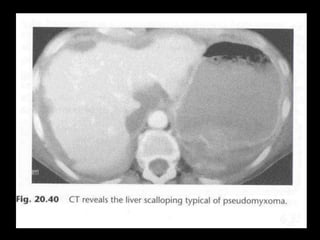

CT

Scalloping phenomenon on the liver and

spleen

CT Scalloping phenomenon onthe liver and spleen

Scalloping phenomenon onthe liver and spleen